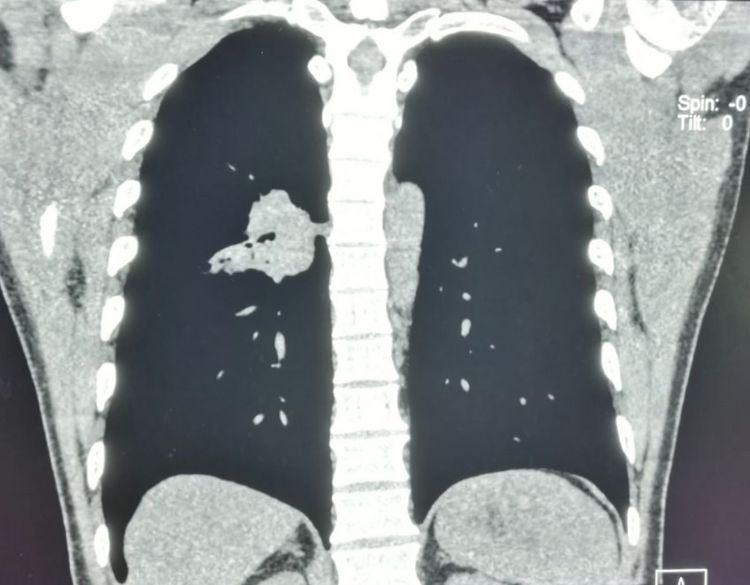

今年已经是两整年了,最近的复查恢复很好,没有复发和转移:

后来老人的亲属拿着片子过来咨询,问右侧胸腔大量可见包裹性积液,是什么意思?

这其实是一个术后残腔,不是复发或转移,不必紧张。